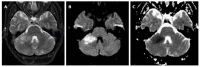

We describe common and less common diseases that can cause magnetic resonance signal abnormalities of middle cerebellar peduncles (MCP), offering a systematic approach correlating imaging findings with clinical clues and pathologic mechanisms. Myelin abnormalities, different types of edema or neurodegenerative processes, can cause areas of abnormal T2 signal, variable enhancement, and patterns of diffusivity of MCP. Pathologies such as demyelinating disorders or certain neurodegenerative entities (e.g., multiple system atrophy or fragile X-associated tremor-ataxia syndrome) appear to have predilection for MCP. Careful evaluation of concomitant imaging findings in the brain or brainstem; and focused correlation with key clinical findings such as immunosuppression for progressive multifocal leukoencephalopahty; hypertension, post-transplant status or high dose chemotherapy for posterior reversible encephalopathy; electrolyte disorders for myelinolysis or suspected toxic-drug related encephalopathy; would yield an appropriate and accurate differential diagnosis in the majority of cases.